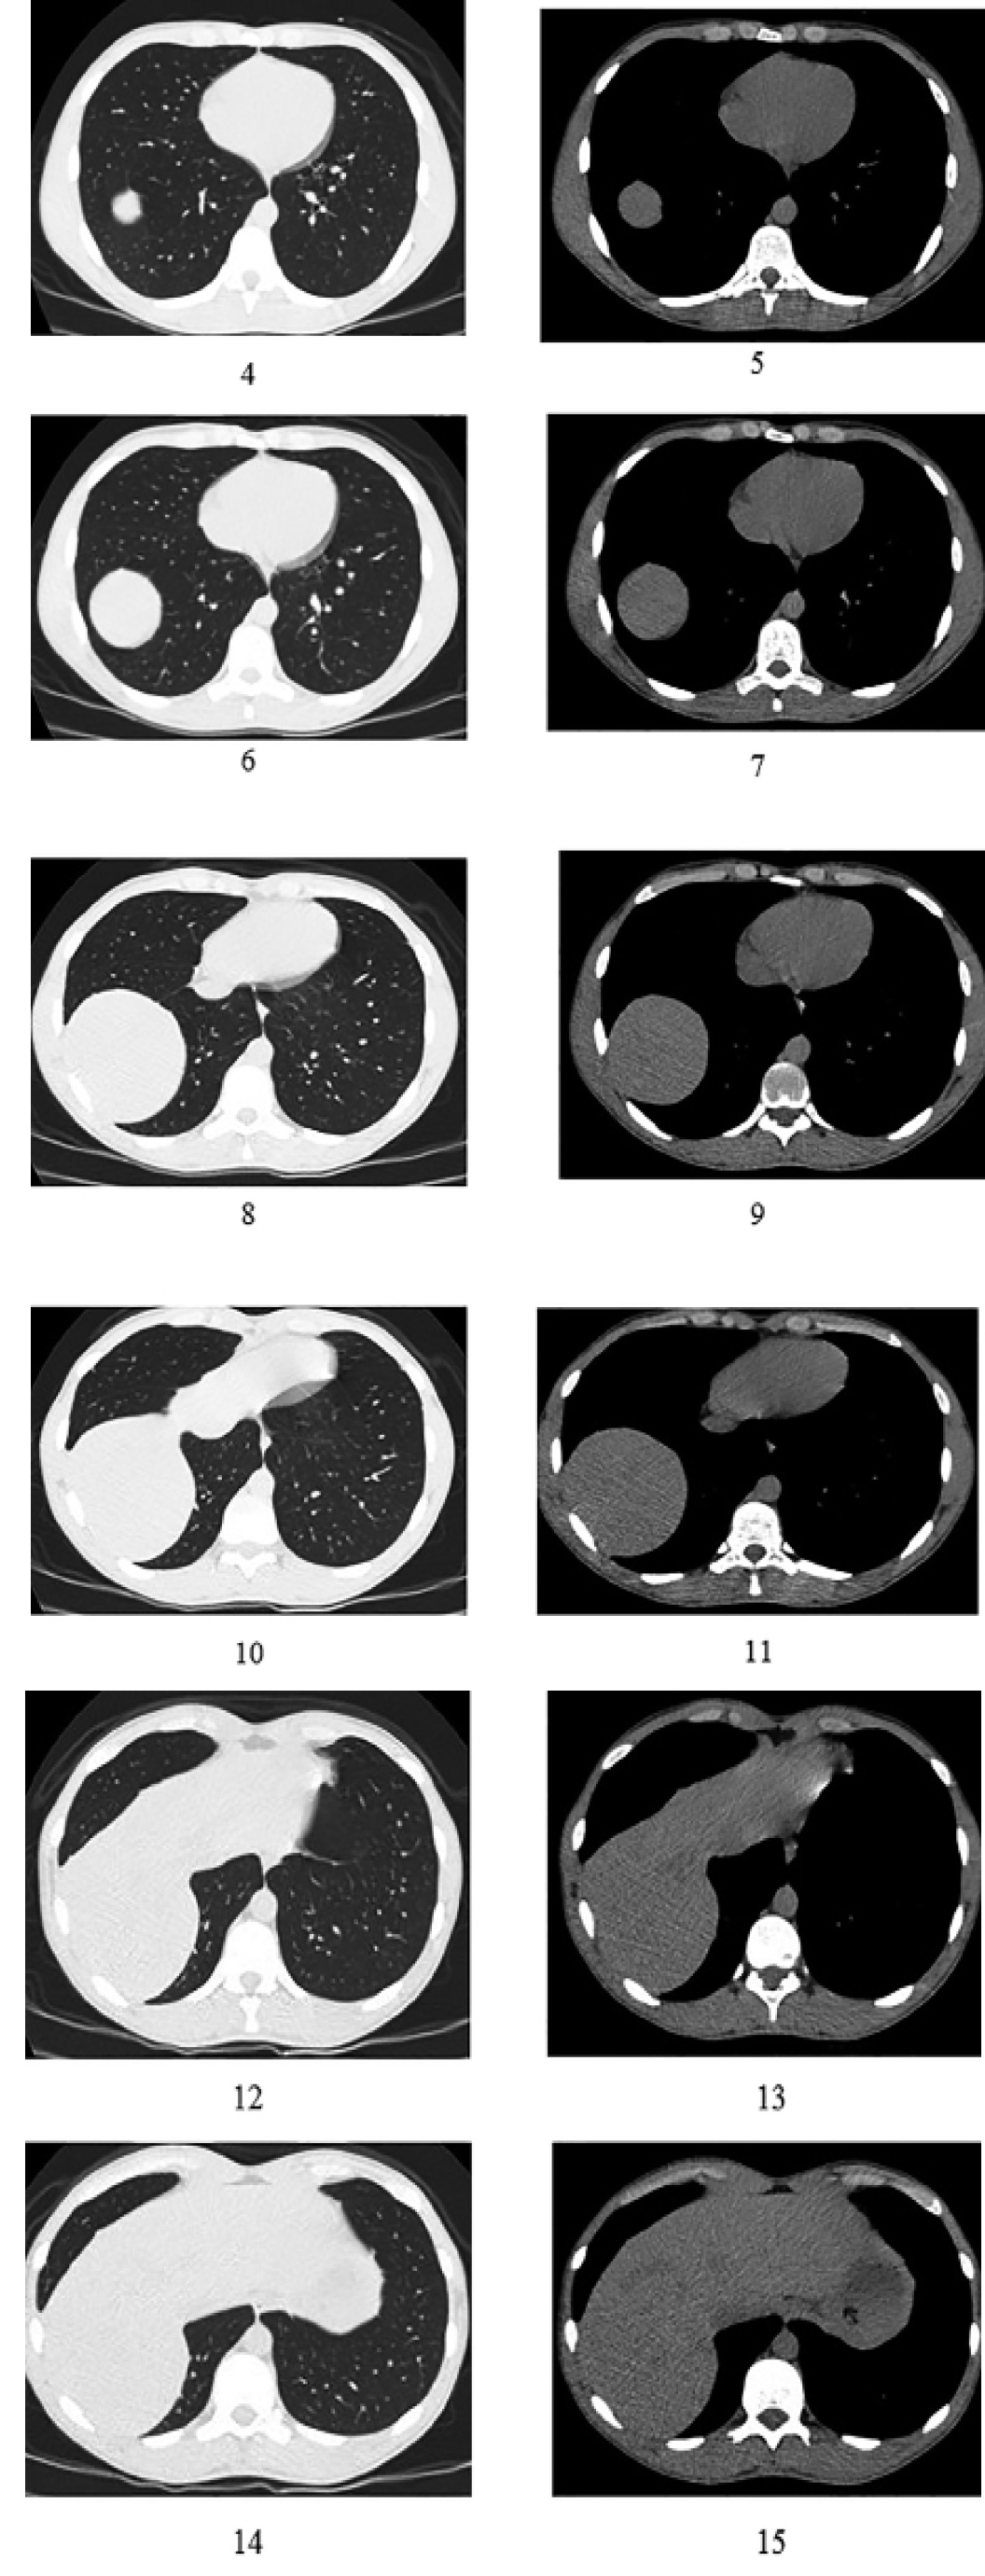

Для дальнейшей верификации диагноза выполнена спиральная компьютерная томография органов грудной, брюшной полостей, забрюшинного пространства и таза с применением внутривенного контрастирования (рис. 4–15).

Рис. 4–15. Компьютерная томография высокого разрешения органов грудной полости пациента Н. в режимах легочного и мягкотканого окон

При спиральной компьютерной томографии органов грудной полости свежих очаговых и инфильтративных изменений не выявлено. Ход и проходимость трахеи, главных и долевых бронхов не нарушены. Средостение не смещено, не расширено. Визуализируется ткань вилочковой железы размерами 1,3×1,6 см. Внутригрудные и подмышечные лимфатические узлы не увеличены. Жидкости в плевральных полостях и полости перикарда не выявлено. Костные травматические и деструктивные изменения не определяются.

При спиральной компьютерной томографии органов брюшной полости и забрюшинного пространства с последующим введением контрастного вещества (ультравист 370–100 мг) определяется грыжевой дефект правой половины купола диафрагмы с пролоббированием правой доли печени в грудную полость. Размеры грыжевых ворот 8,2 см, грыжевого выпячивания – 8,4×9,5×10,0 см. Плотностные показатели печени составляют 49–58HU, структура однородная, контрастирование равномерное, краниокаудальный размер 13,8 см. Желчный пузырь S-образной формы, содержимое пузыря однородное, стенка не утолщена. Селезенка в размерах не увеличена, плотностные показатели не изменены и составляют 39–45 HU, структура однородная, контрастирование равномерное. Поджелудочная железа не увеличена, дольчатая, контур железы четкий. Парапанкреатическая клетчатка не изменена. Надпочечники не увеличены, дифференцируются на тело и ножки, новообразование в них не определяется. Местоположение почек обычное, паренхима не истончена. Дифференцировка на корковое и мозговое вещество сохранена. Чашечно-лоханочные системы не расширены. Рентгенконтрастные конкременты не выявлены. Параренальная клетчатка не уплотнена. Мочевой пузырь сокращен, стенка его не изменена. Предстательная железа однородная, размеры 3,2×3,4 см. Клетчатка малого таза не упллотнена. Лимфатические узлы не увеличены. Визуализируются паховые лимфатические узлы, размерами справа до 0,6×1 см, слева – до 0,7×1 см. Свободной жидкости в брюшной полости и полости таза не выявлено. Костные травматические и деструктивные изменения не определяются.

В области правой половины купола диафрагмы визуализируется диафрагмальная грыжа, содержимое грыжевого мешка – печень, нельзя исключить травматический генез формирования грыжи.